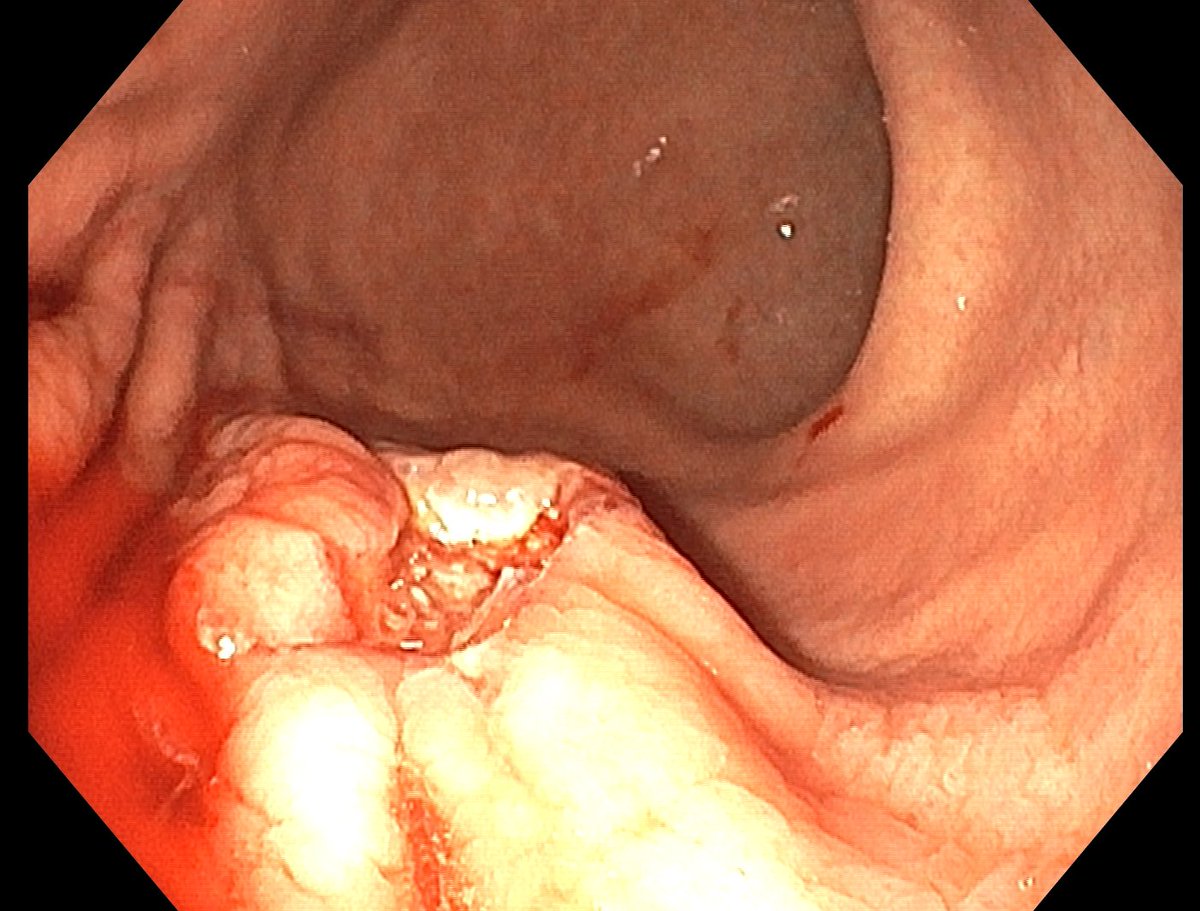

1. Antrum, low grade dysplasia. Removed via ESD. Specimen 43x32mm / dysplasia 20x13mm. R0